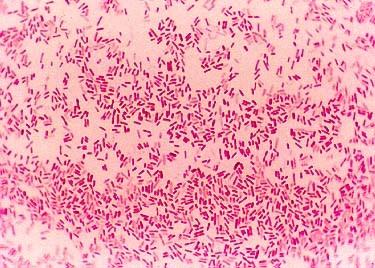

Name the bacteria based on the shape you can see on the picture.

Coccus

Bacillus

Spirillum

Streptococcus

Staphylococcus

Coccobacillus

Streptobacillus